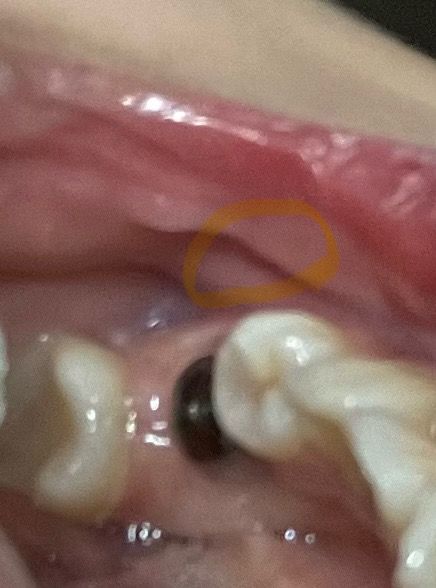

동그라미친 부분이 이물감 느낌이 드는 부분입니다... 잘 아물고 있는거겠죠?ㅠㅠ

현재 사진만으로는 정확한 판단이 어렵습니다. 임플란트 식립 위치가 너무 바깥쪽으로 있는 경우에 임플란트가 일부 노출되어 이러한 증상이 나타날 수도 있으나 현재 사진만으로는 섣불리 판단하기에 어려움이 있습니다. 계속해서 불편감이 있다면 dental-ct 등의 촬영을 권해드립니다.

저부위는 임플란트 식립을 한곳과는 크게 연관성은 없는곳입니다. 하지만 임플란트가 실패햇을경우에 그쪽이 전체적으로 불편감이 잇을수도 잇으니 치과에 가셔서 엑스레이 사진을 한번 찍어보세요.

골이식을 하게 되면 골 이식을 한 위에 잇몸이 떠 있는 느낌이 들 수 있습니다.

사진상으로 크게 문제가 있어보이지는 않으나 통증이 계속 지속되는 경우에는 염증이 있을 가능성이 있기에 치과에 방문하여 상태를 체크해보는 것이 좋습니다.

3. 사진상에서는 정상 치조점막 구조입니다.

4. 뼈이식한 부위가 느껴지는 것일 수도 있는데 사진에서 동그라미 쳐진 부분은 잇몸보다는 잇몸 하방의 치조점막에 가깝습니다